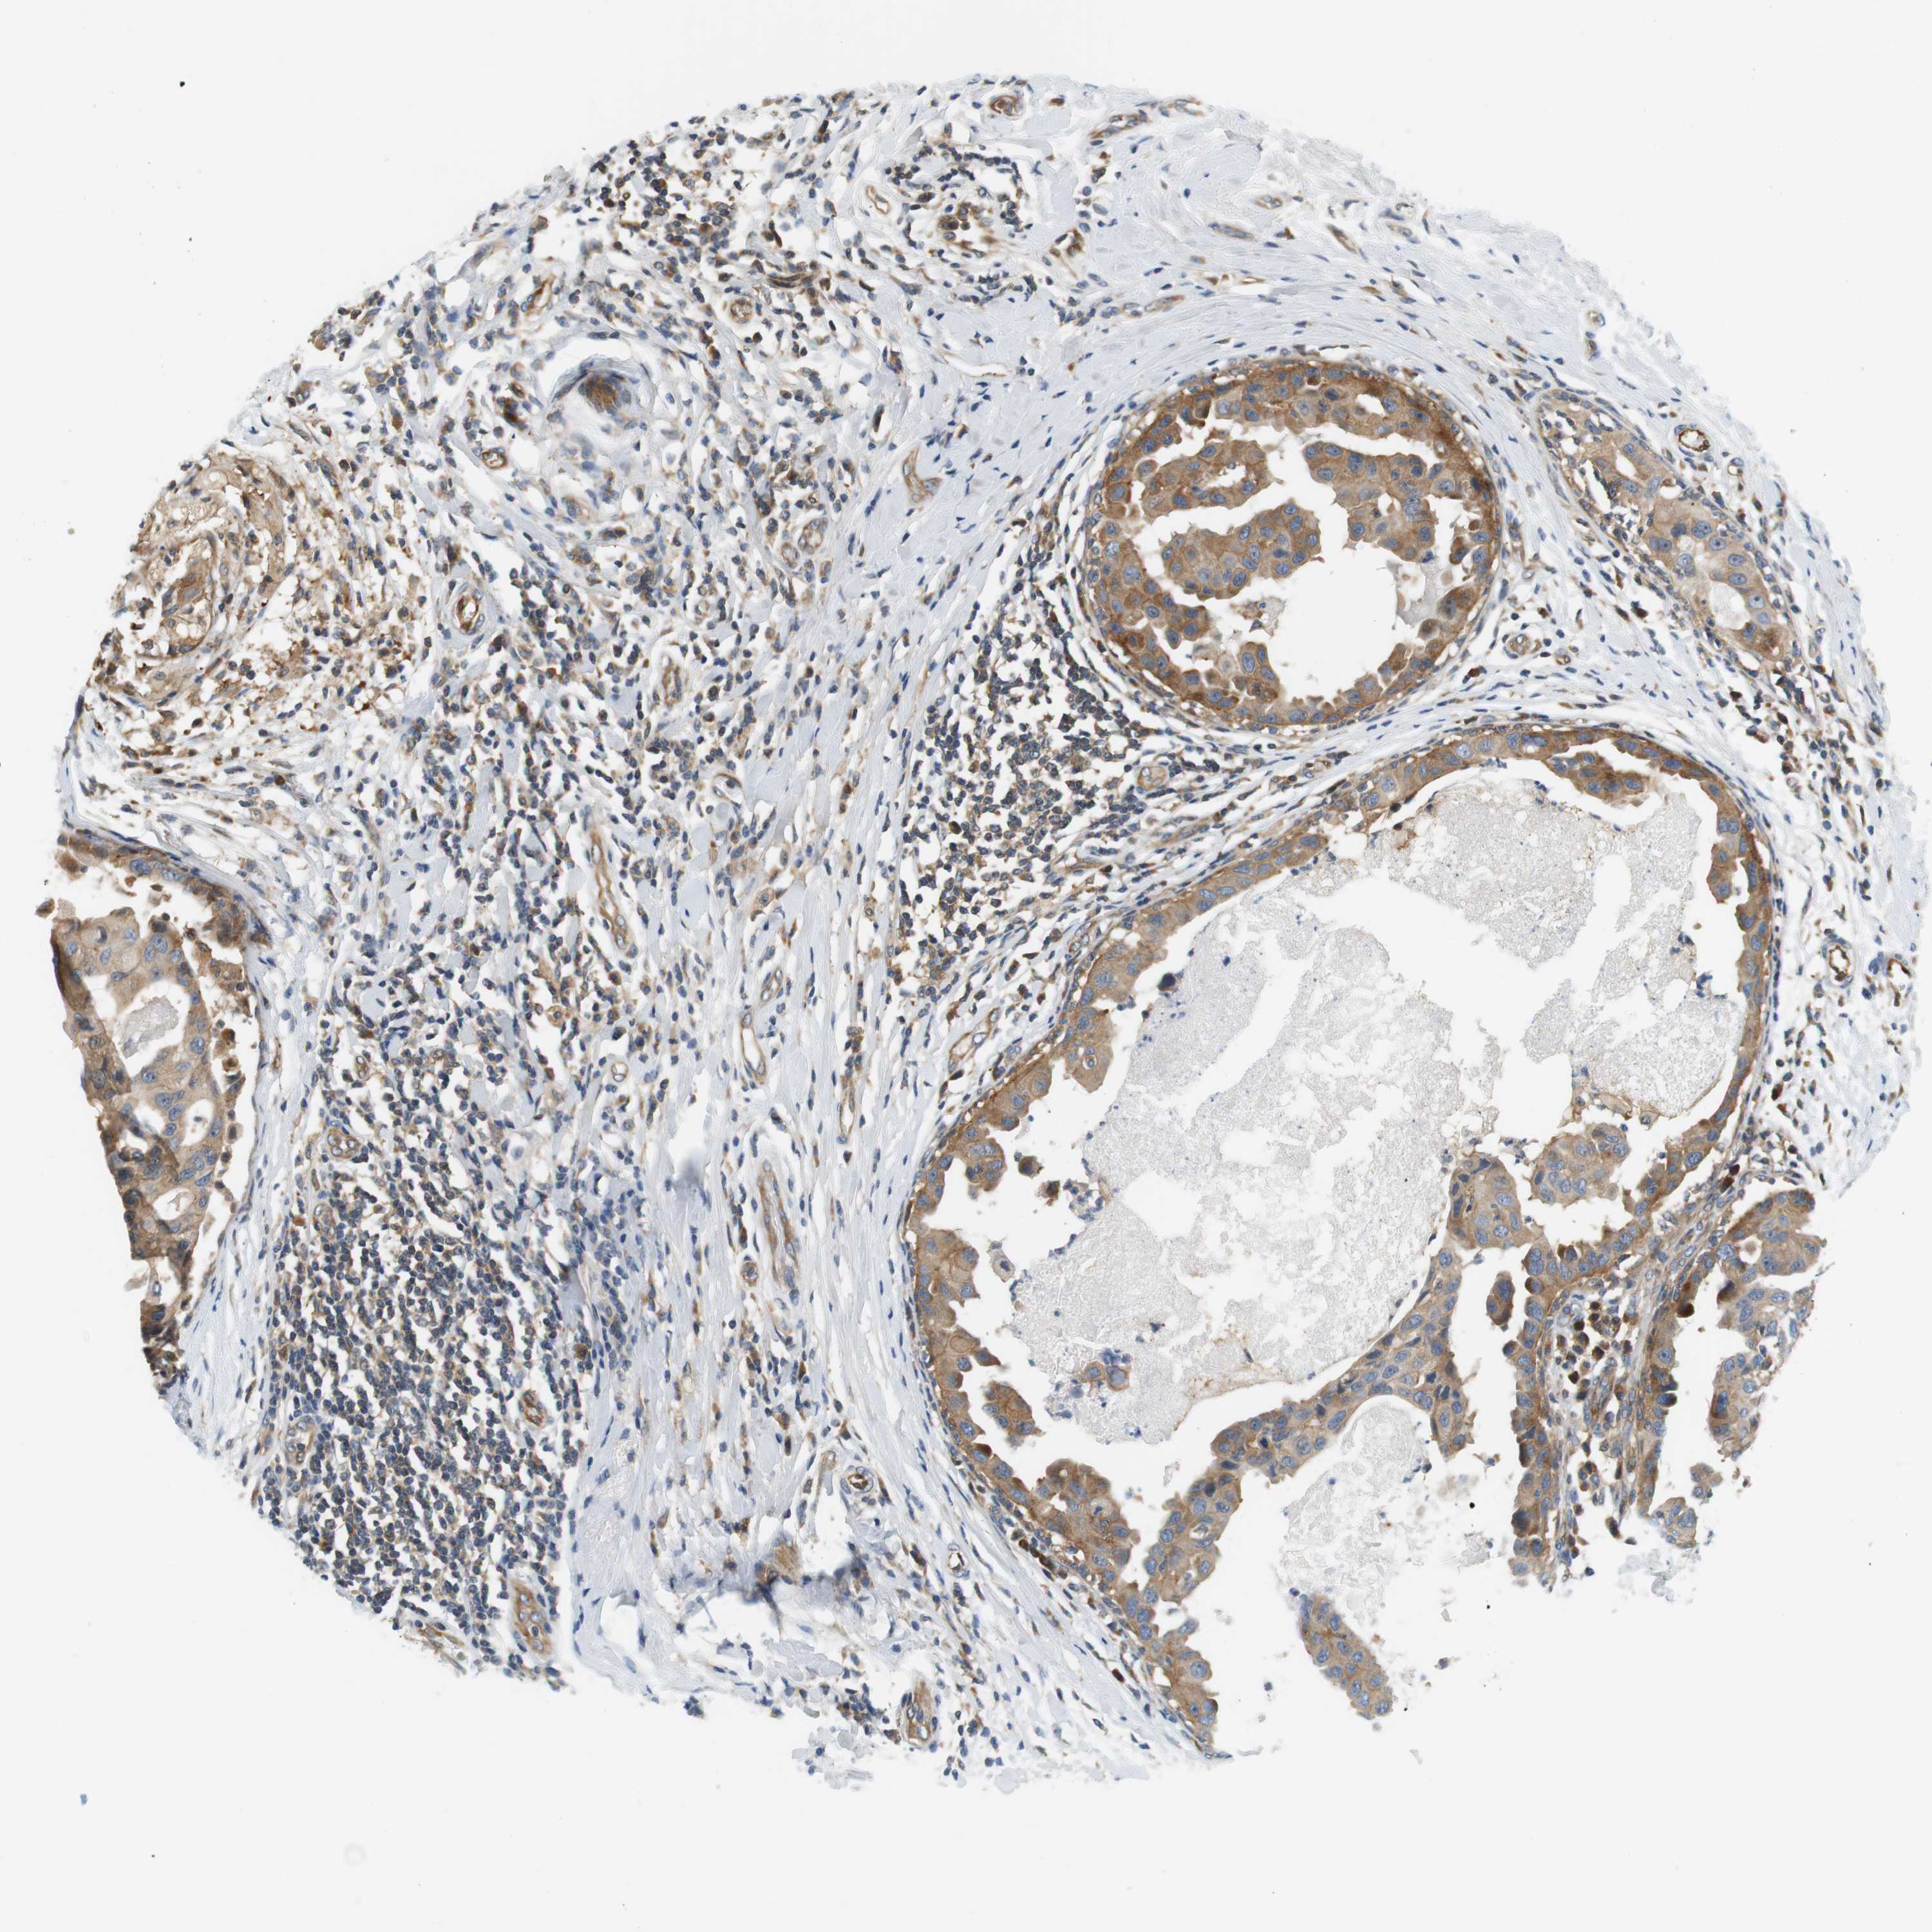

CANCER BREAST CANCER Show tissue menu

BRCA TCGA BRCA VALIDATION PROTEIN EXPRESSION